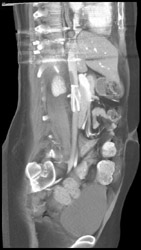

VRT of Chest Wall Collaterals